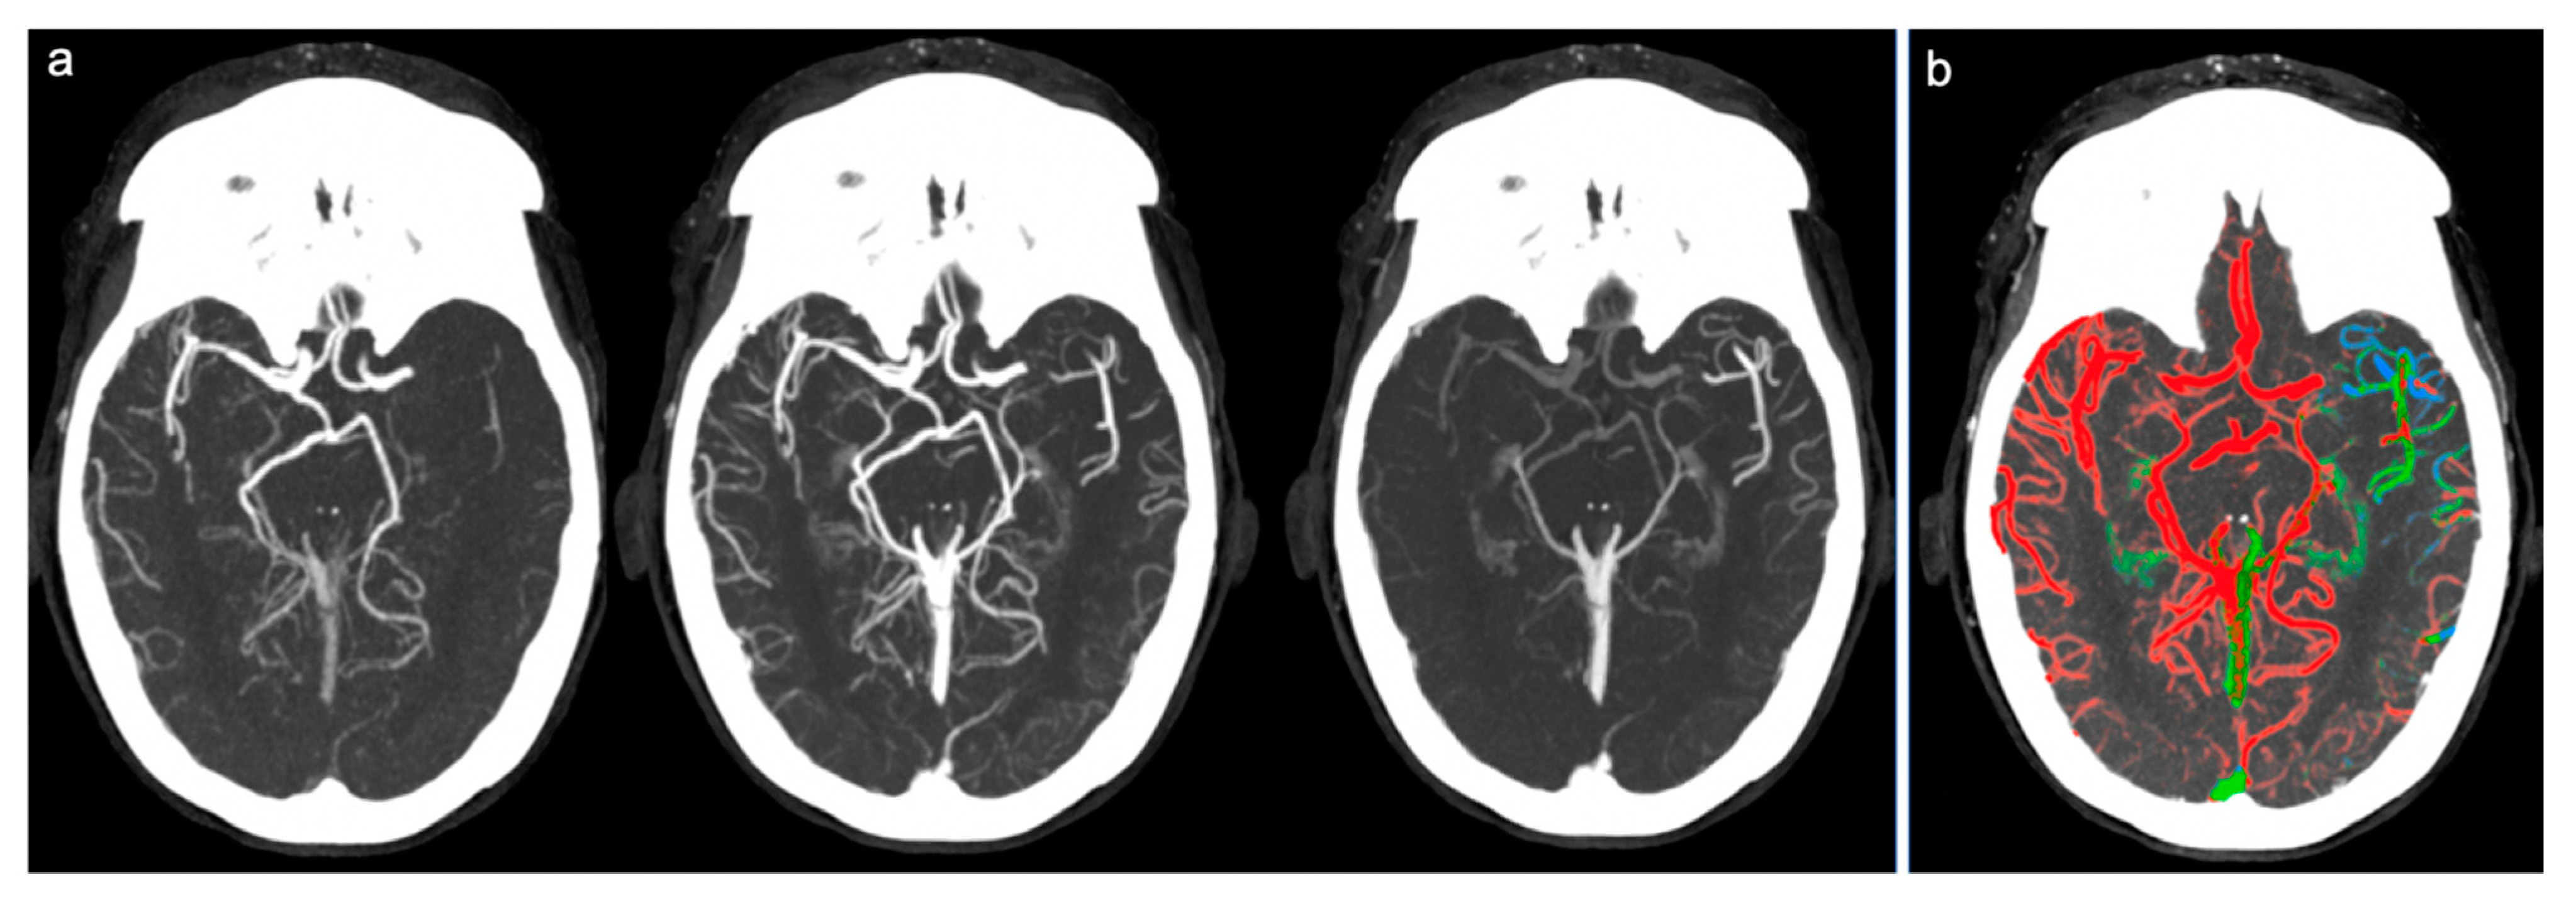

Figure 3.

Example of poor collateral circulation at ColorViz. (a) mCTA shows a left-sided M1 segment occlusion with poor pial artery filling; (b) ColorViz map shows reduced extension of collateral circles vessels in the affected territory downstream from the occlusion (score of 1).